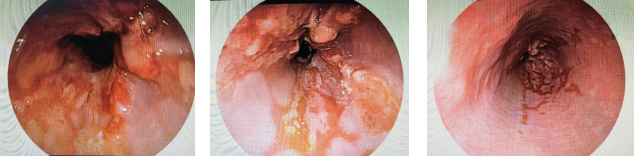

最終,在我院消化內(nèi)鏡中心進行了無痛舒適化高清胃鏡檢查后,張先生被確診為食管中低分化腺癌。

“食管癌早期癥狀與反流性食管炎有許多相似性,都可能出現(xiàn)胸骨后反酸、燒心等不適,容易導致誤診、漏診。大家切不可對胃食管反流病掉以輕心,別把反流不當回事,即使已經(jīng)胃鏡確診胃食管反流病,也要定期復查胃鏡?!?/span>

繆曉峰副主任醫(yī)師提醒,食管惡性腫瘤病理多以鱗癌為主,而食管腺癌相對少見,其好發(fā)部位多位于食管下段(靠近胃賁門),常與胃食管反流病及巴雷特食管相關(guān)。